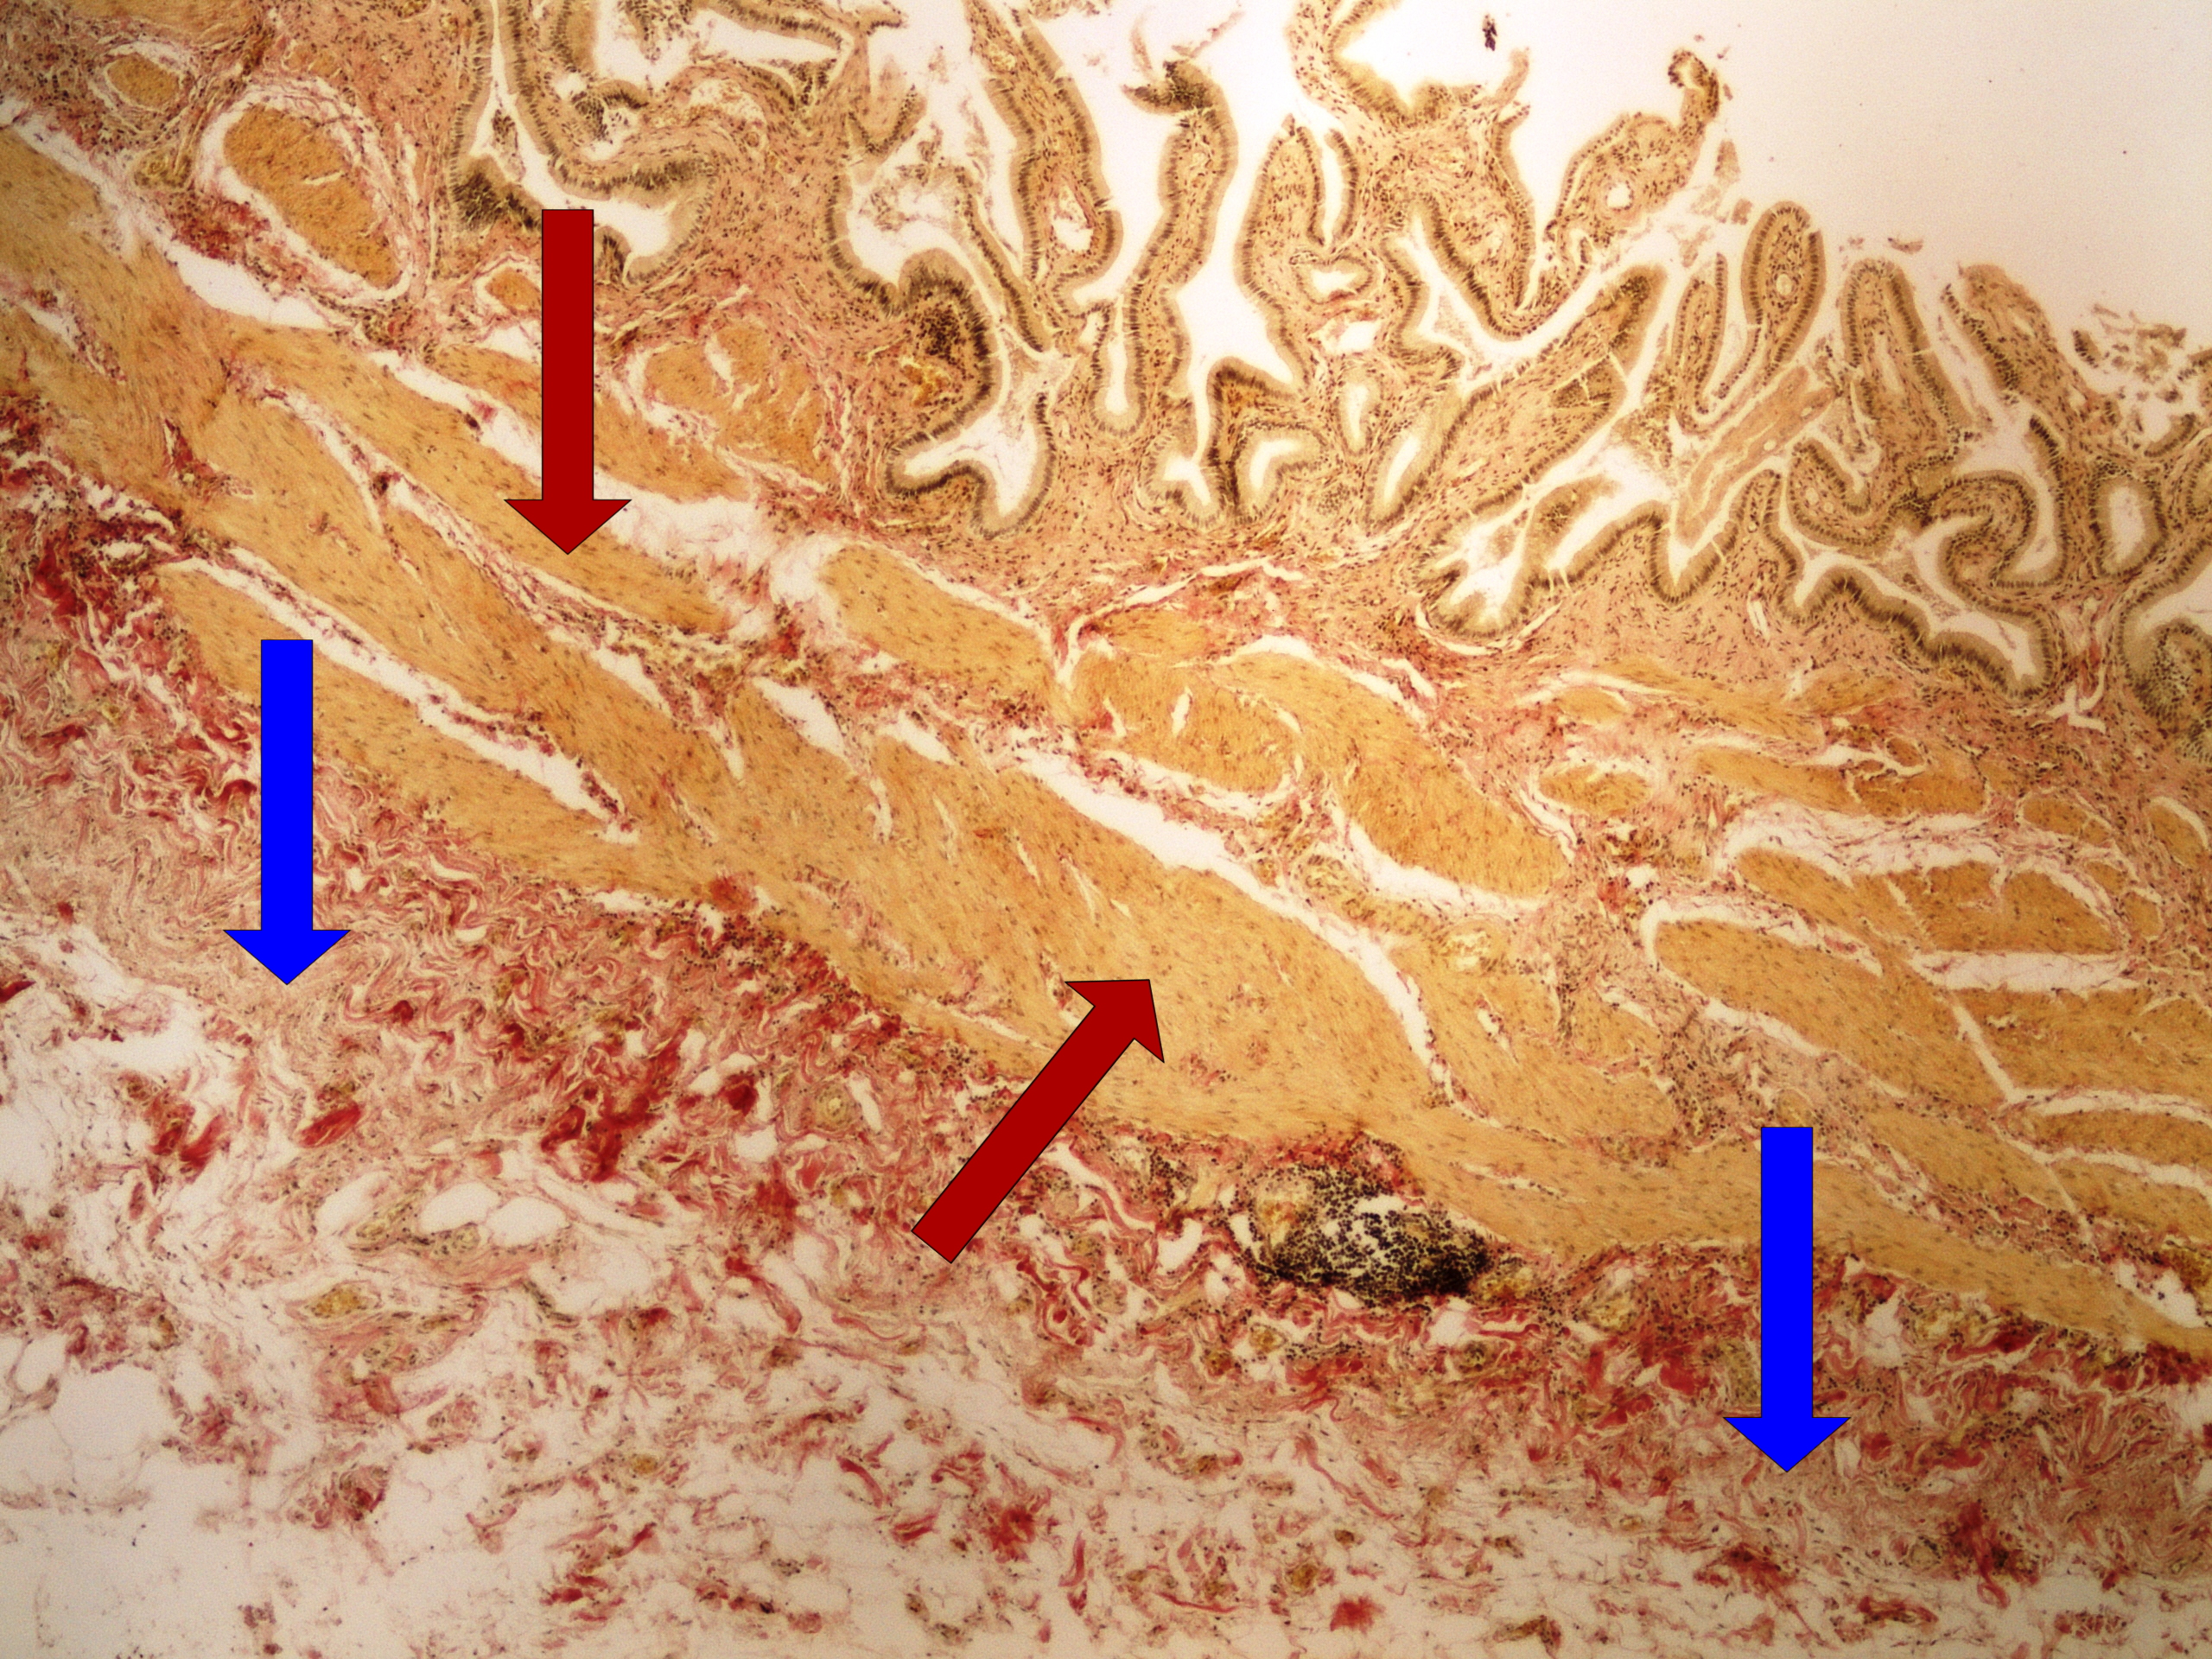

Preparát č.11 a č.12 - barvení van Gieson (žlučník)

Struktury

- hladká svalovina

- vazivo